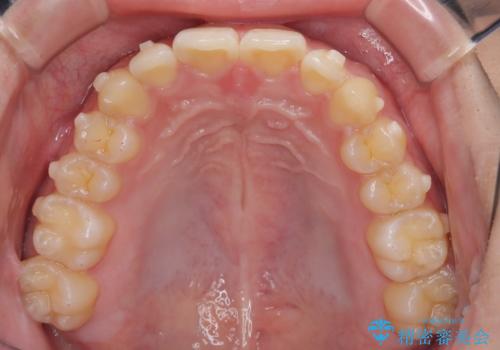

マウスピース矯正で前歯のガタツキを改善! 短期間で治療完了

- 前歯のガタツキが気になるとのことで来院されました。

マウスピース矯正で治療することとしました。

- 1年3ヶ月